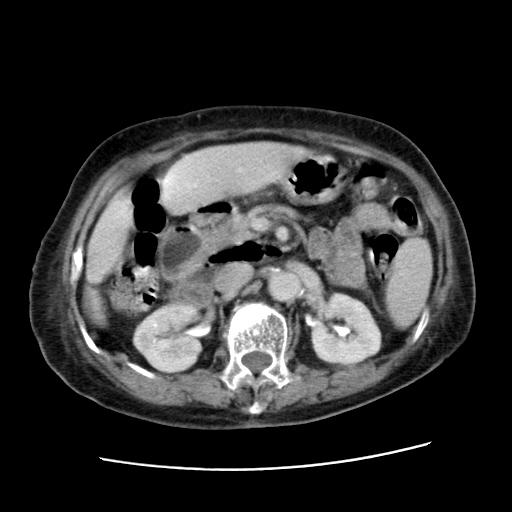

女,77.无不适

肝脏变异、异位胆囊,肝右叶肝内胆管结石并肝内胆管扩张。

肝右叶肝内胆管结石并肝内胆管扩张。

肝右叶肝内胆管结石并肝内胆管扩张

胆总管扩张

肝右叶肝内胆管结石并肝内胆管扩张。胆总管下段梗阻,考虑壶腹部占位。

右侧肝内胆管局限性扩张,其内密度不均匀,扩张的胆管壁增厚,考虑肝内胆管炎合并结石可能性大

肝右叶肝内胆管结石并肝内胆管扩张。胆总管下段梗阻,考虑壶腹部占位。支持